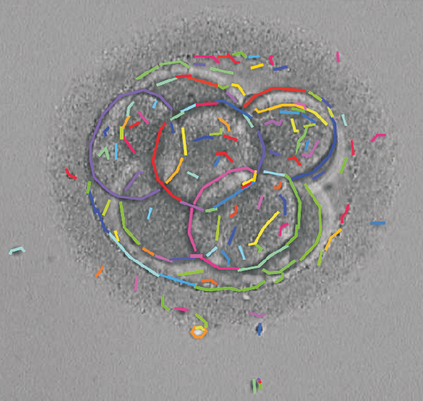

We present a novel method for identification of the boundary of embryonic cells (blastomeres) in Hoffman Modulation Contrast (HMC) microscopic images that are taken between day one to day three. Identification of boundaries of blastomeres is a challenging task, especially in the cases containing four or more cells. This is because these cells are bundled up tightly inside an embryo's membrane and any 2D image projection of such 3D embryo includes cell overlaps, occlusions, and projection ambiguities. Moreover, human embryos include fragmentation, which does not conform to any specific patterns or shape. Here we developed a model-based iterative approach, in which blastomeres are modeled as ellipses that conform to the local image features, such as edges and normals. In an iterative process, each image feature contributes only to one candidate and is removed upon being associated to a model candidate. We have tested the proposed algorithm on an image dataset comprising of 468 human embryos obtained from different sources. An overall Precision, Sensitivity and Overall Quality (OQ) of 92%, 88% and 83% are achieved.